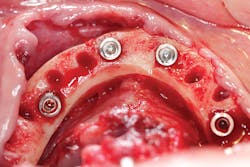

- All-on-4 (AO4) or a full-arch hybrid prosthesis that is fixed (figures 4 and 5).